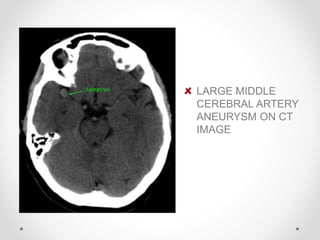

LARGE MIDDLE

CEREBRAL ARTERY

ANEURYSM ON CT

IMAGE